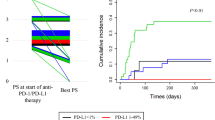

We investigated the clinical significance of plasma sPD-L1 levels focusing on the origin of sPD-L1 in peripheral blood. First, patients who underwent radical surgery for invasive carcinoma (n = 55) (Supplementary Table 2) were classified into two groups according to preoperative plasma sPD-L1 levels: the high sPD-L1 group (≥ 80 pg/mL) and the low sPD-L1 group (< 80 pg/mL), as described earlier. Kaplan–Meier analysis revealed that postoperative RFS tended to be shorter in the high sPD-L1 group (n = 18) than in the low sPD-L1 group (n = 37), which had 5-year relapse-free probabilities of 58.8% and 67.9%, respectively (P = 0.442, 95% confidence interval [CI]: 0.268–1.785) (Fig. 4a).

In patients who underwent radical surgery, including lobectomy and dissection of regional lymph nodes, for invasive non-small cell lung cancer with pathological stages of IA to IIIA (n = 55), a correlation between preoperative plasma soluble PD-L1 (sPD-L1) levels and relapse-free survival (RFS) after surgery analyzed by the Kaplan–Meier method. Red and blue lines indicate data from patients with high (≥ 80 pg/mL) and low (< 80 pg/mL) plasma preoperative sPD-L1 levels, respectively. b Correlation between the PD-L1 expression intensity of tumor cells and RFS after surgery analyzed by the Kaplan–Meier method. Red and blue lines in the indicate data from patients with high (H-score ≥ 150) and low (H-score < 150) PD-L1 expression intensity of tumor cells, respectively. c Correlation between the cell density of PD-L1-positive tumor-associated macrophages (TAMs) and RFS after surgery analyzed by the Kaplan–Meier method. Red and blue lines in the indicate data from patients with high (≥ 150/mm2) and low (< 150/mm2) cell density of PD-L1-positive TAMs, respectively

Next, we analyzed the correlation between tcPD-L1 expression intensity and RFS after surgery. Patients were classified into two groups according to the tcPD-L1 expression intensity: the high tcPD-L1 expression group (≥ 150) and the low tcPD-L1 expression group (< 150), as in a previous report [10]. Kaplan–Meier analysis revealed that postoperative RFS tended to be longer for the high tcPD-L1 expression group (n = 17) than for the low tcPD-L1 expression group (n = 38), which had 5-year relapse-free probabilities of 76.5% and 59.3%, respectively (P = 0.241, 95% CI: 0.171–1.587) (Fig. 4b). In contrast with the data of plasma sPD-L1, high tcPD-L1 expression intensity tended to be better prognosis after surgery in NSCLC, which is compatible with our previous data [10].

In addition, we analyzed the correlation between the cell density of PD-L1-positive TAMs and RFS after surgery. Patients were classified into two groups according to the cell density of PD-L1-positive TAMs: the high PD-L1-positive TAMs group (≥ 150/mm2) and the low PD-L1-positive TAMs group (< 150/ mm2) (Area under the curve = 1.000). Kaplan–Meier analysis revealed that postoperative RFS tended to be longer for the low PD-L1-positive TAMs group (n = 30) than for the high PD-L1-positive TAMs group (n = 25), which had 5-year relapse-free probabilities of 72.8% and 54.5%, respectively (P = 0.241, 95% CI: 0.196–1.262) (Fig. 4c).

Different prognoses by the origin of sPD-L1 in peripheral blood

Given that the contributions to RFS after surgery may be distinct between sPD-L1 and tcPD-L1, we next classified the patients into four groups according to preoperative plasma sPD-L1 levels and tcPD-L1 expression intensity, and then analyzed RFS after surgery. Kaplan–Meier analysis revealed that postoperative RFS was significantly shorter for patients in the high sPD-L1–low tcPD-L1 group (n = 10) compared with those in the high sPD-L1–high tcPD-L1 group (n = 8), which had 5-year relapse-free probabilities of 33.3% and 87.5%, respectively (P = 0.016, Hazard ratio; 0.114, 95% CI; 0.130–0.964) (Fig. 5a). These data suggest that among NSCLC patients with high preoperative plasma sPD-L1 levels, those whose plasma sPD-L1 was presumably derived from high tcPD-L1 expression might have a better prognosis after surgery, given that postoperative RFS tended to be longer for the high tcPD-L1 expression group than for the low tcPD-L1 expression group (Fig. 4b). In contrast, for NSCLC patients with high preoperative plasma sPD-L1 and low tcPD-L1 expression, PD-L1-positive TAMs must be responsible for the elevated sPD-L1 level in peripheral blood and also contribute to poor prognosis, given that postoperative RFS tended to be shorter for the high PD-L1-positive TAMs group than for the low PD-L1-positive TAMs group (Fig. 4c). In fact, in the high sPD-L1–low tcPD-L1 group (n = 10), the cell density of PD-L1-positive TAMs was significantly high compared with that in the high sPD-L1–high tcPD-L1 group (n = 8) (median ± SD: 246.4 ± 149.5 vs.76.6 ± 48.1 counts/mm2, respectively, P = 0.003) (Fig. 5b).

Patients who underwent radical surgery, including lobectomy and dissection of regional lymph nodes, were classified into four groups according to preoperative plasma soluble PD-L1 (sPD-L1) levels and the PD-L1 expression intensity of tumor cells, and then a relapse-free survival after surgery was analyzed by Kaplan–Meier method. Red and blue lines indicate the data of patients with high preoperative sPD-L1 levels in plasma (≥ 80 pg/mL) and high (H-score ≥ 150) or low (H-score < 150), respectively. Green and orange lines indicate the data from patients with low preoperative sPD-L1 levels in plasma (< 80 pg/mL) and high or low PD-L1 expression intensity of tumor cells, respectively. b The cell density of PD-L1-positive tumor-associated macrophages (TAMs). Red bars indicate the median cell density of PD-L1-positive TAMs. c The levels of sPD-L1 that were secreted from type 1 and type 2 macrophages. The cells were generated in vitro and activated by lipopolysaccharide, then the sPD-L1 levels in the supernatant were measured by ELISA